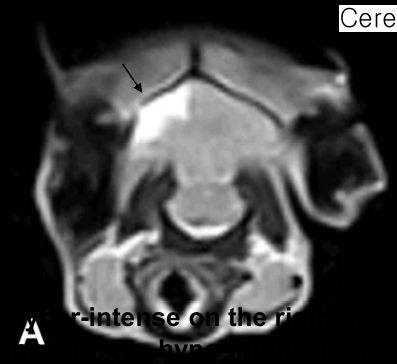

| MRI (transverse) |

|---|

![]() |

| - ๊ฐ์ชฝ๋์ค์ด ์ ์๋ณด๋ค ํ์ฅ๋์ด ์์. - Tumor ์กด์ฌ : T2 image์์ ์ข ์ ์ถ์ โ FLAIR๋ก ํ์คํ ํ์ธ - ๋์ diencepalon ์์ญ์ ํฐ tumor ์กด์ฌ (๊ฐ๋์์๋ hypothalamus๋ pituitary gland์ ์ข ์ ์์ ๊ฐ๋ฅ์ฑ ๋์ : ํธ๋ฅด๋ชฌ ์งํ(Cushingโs dz) ๊ฐ๋ฅ์ฑ ๋์ โ ๋ด๋ถ๋น ์ฆ์ ๋ณด์ผ ๊ฒ) - Hydrocephalus๋ ์ฌํ์ง ์์ ์์ค์ผ๋ก ์์ - Dural tail sign์ ๋ณด์ด์ง ์์ : Meningioma < hypothalamus tumor |

Thalamus, hypothalamus์ mass (1.5 X 1.6cm) Hydrocephalus (23%, moderate)